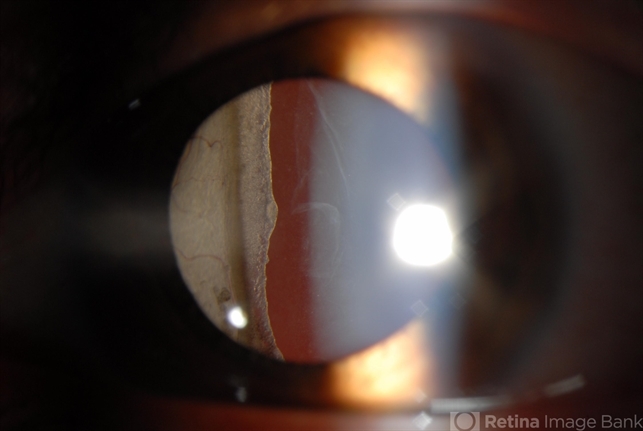

- giant retinal tear, membranous vitreous, Stickler Syndrome

- Slit lamp photograph